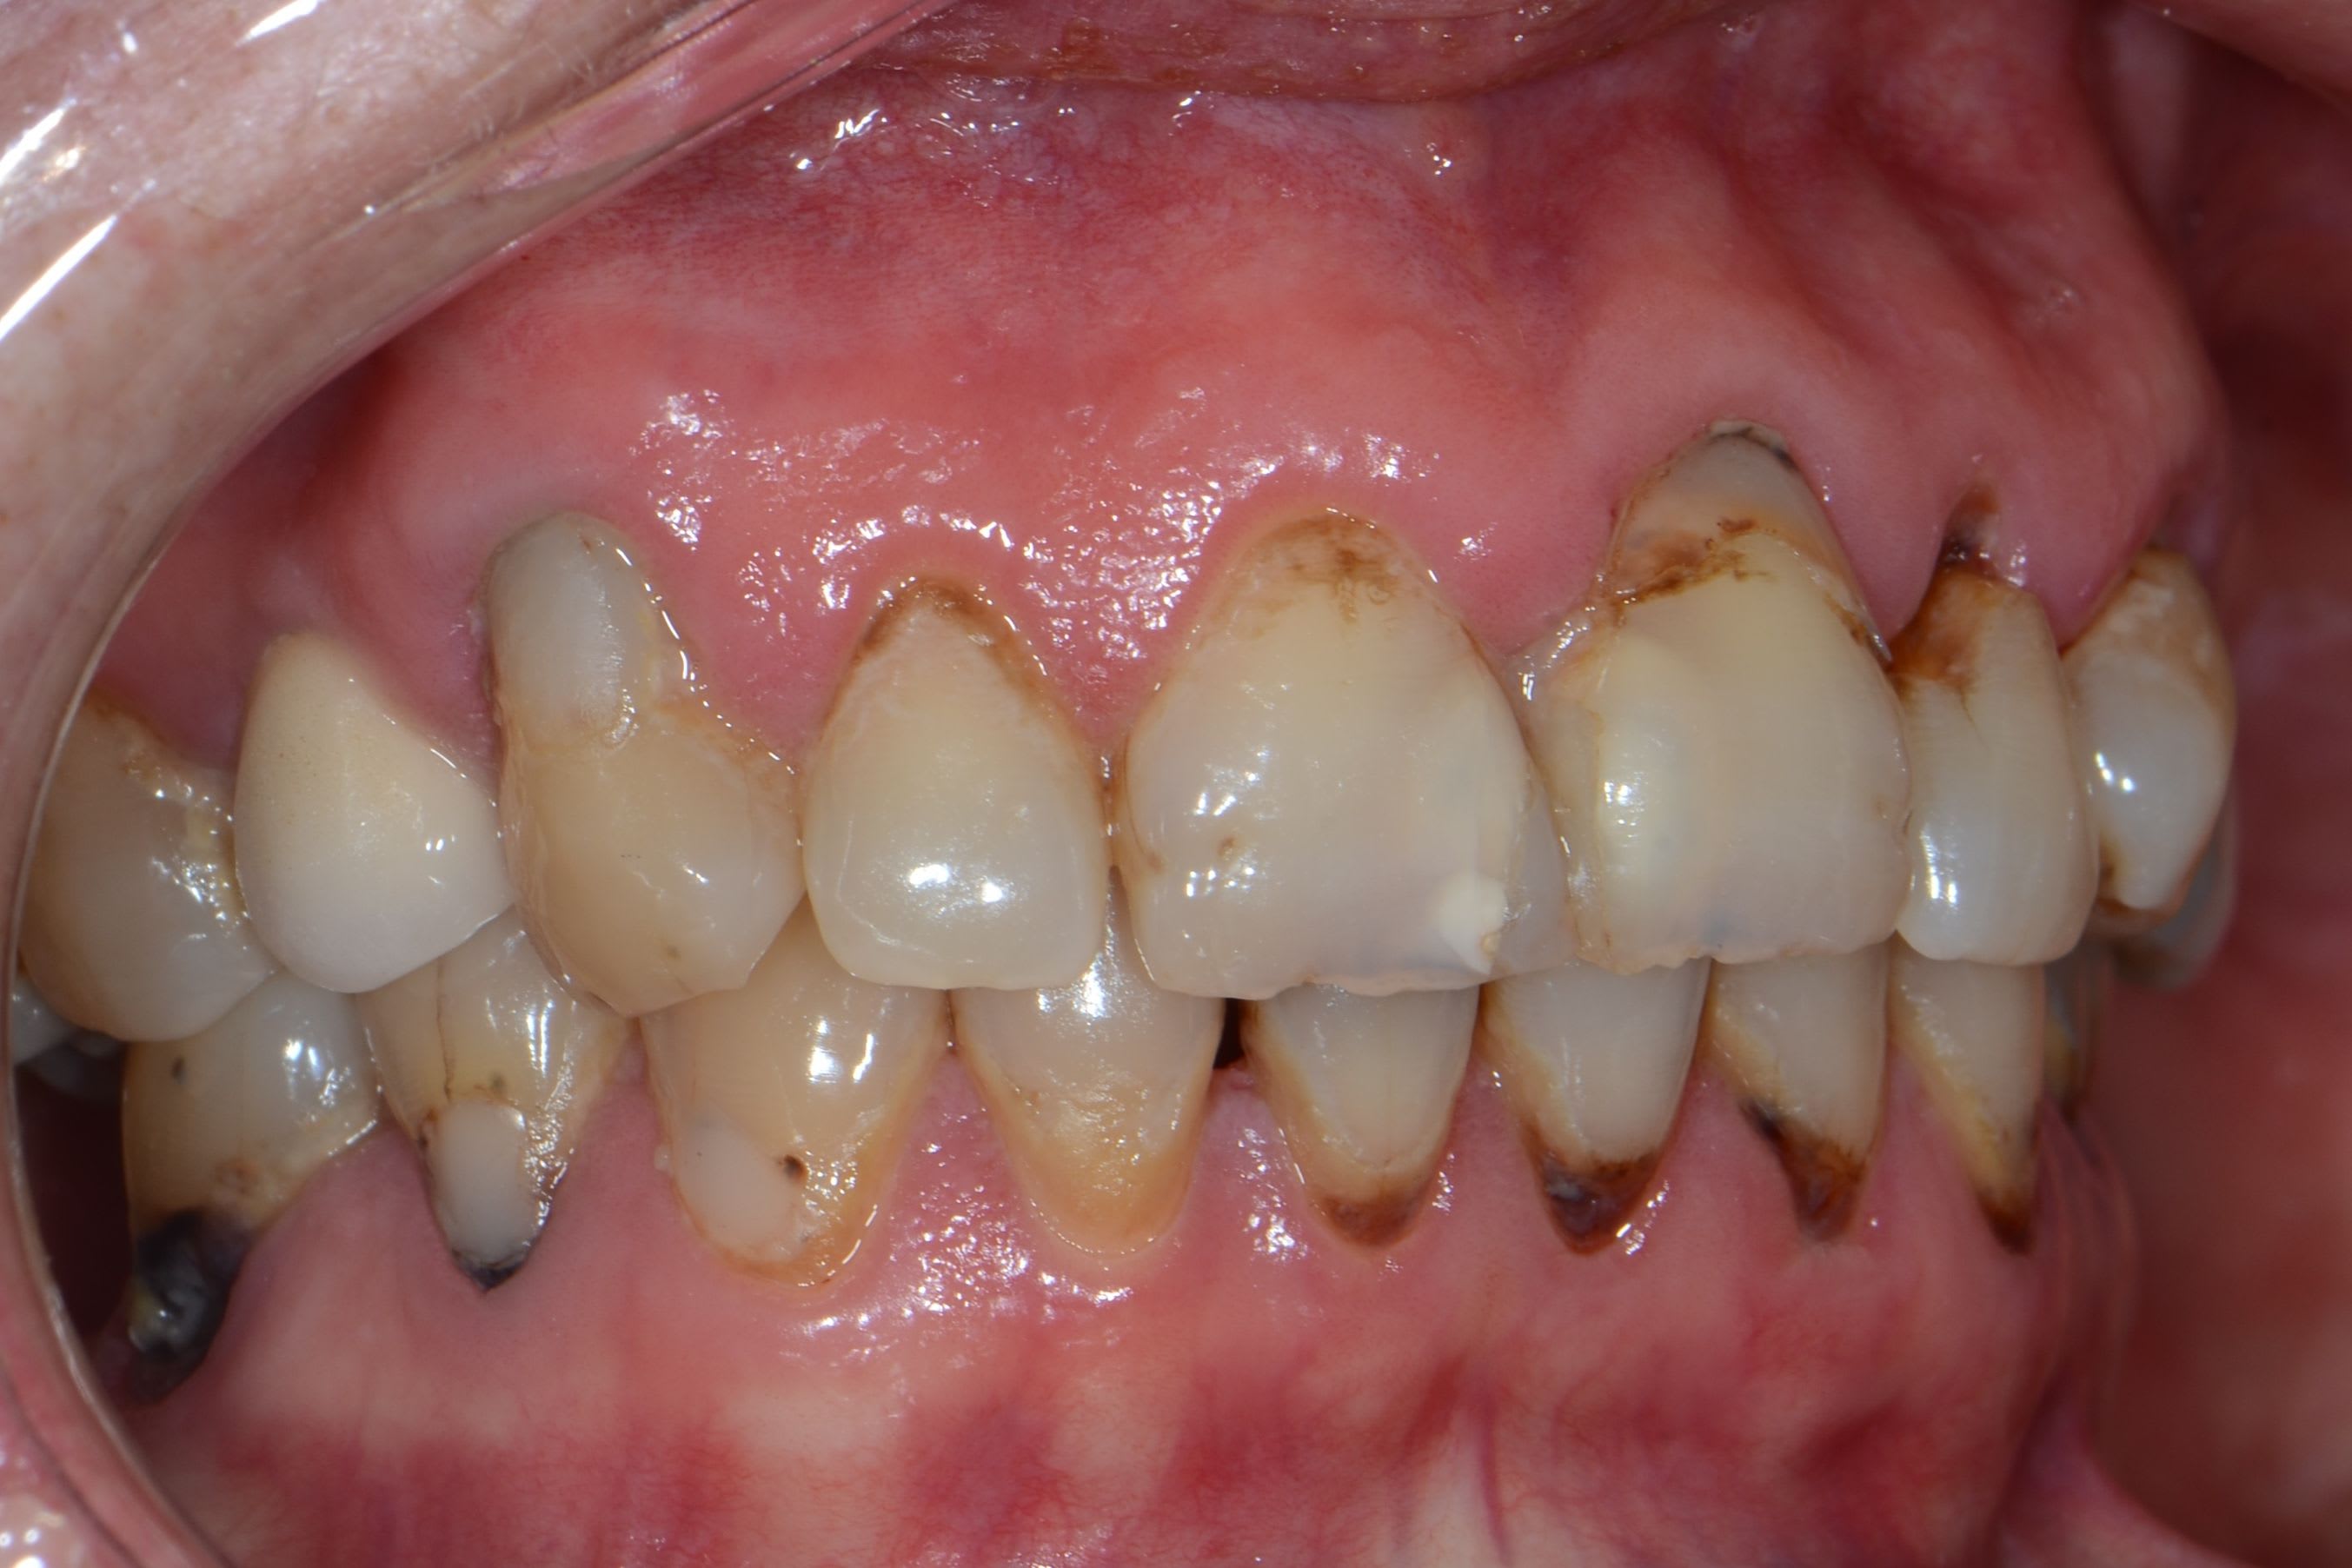

Nouvelle patiente 60 ans, pas de tabac, pas d'habitudes alimentaires prédisposantes mais syndrôme sec, très peu de salivation et ce depuis 2 ans.

A l'examen clinique, caries de collets typiques, la 45 a du être dévitalisée. Les caries sont plus importantes cliniquement que radiologiquement. Par ex les incisives mand étaient presque intégralement cariées en linguale (?).

Je lui ai fais un bilan et ai décidé de soigner les caries de collet au CVI (GC Equia forte). La 24 et 45 seront couronnées.